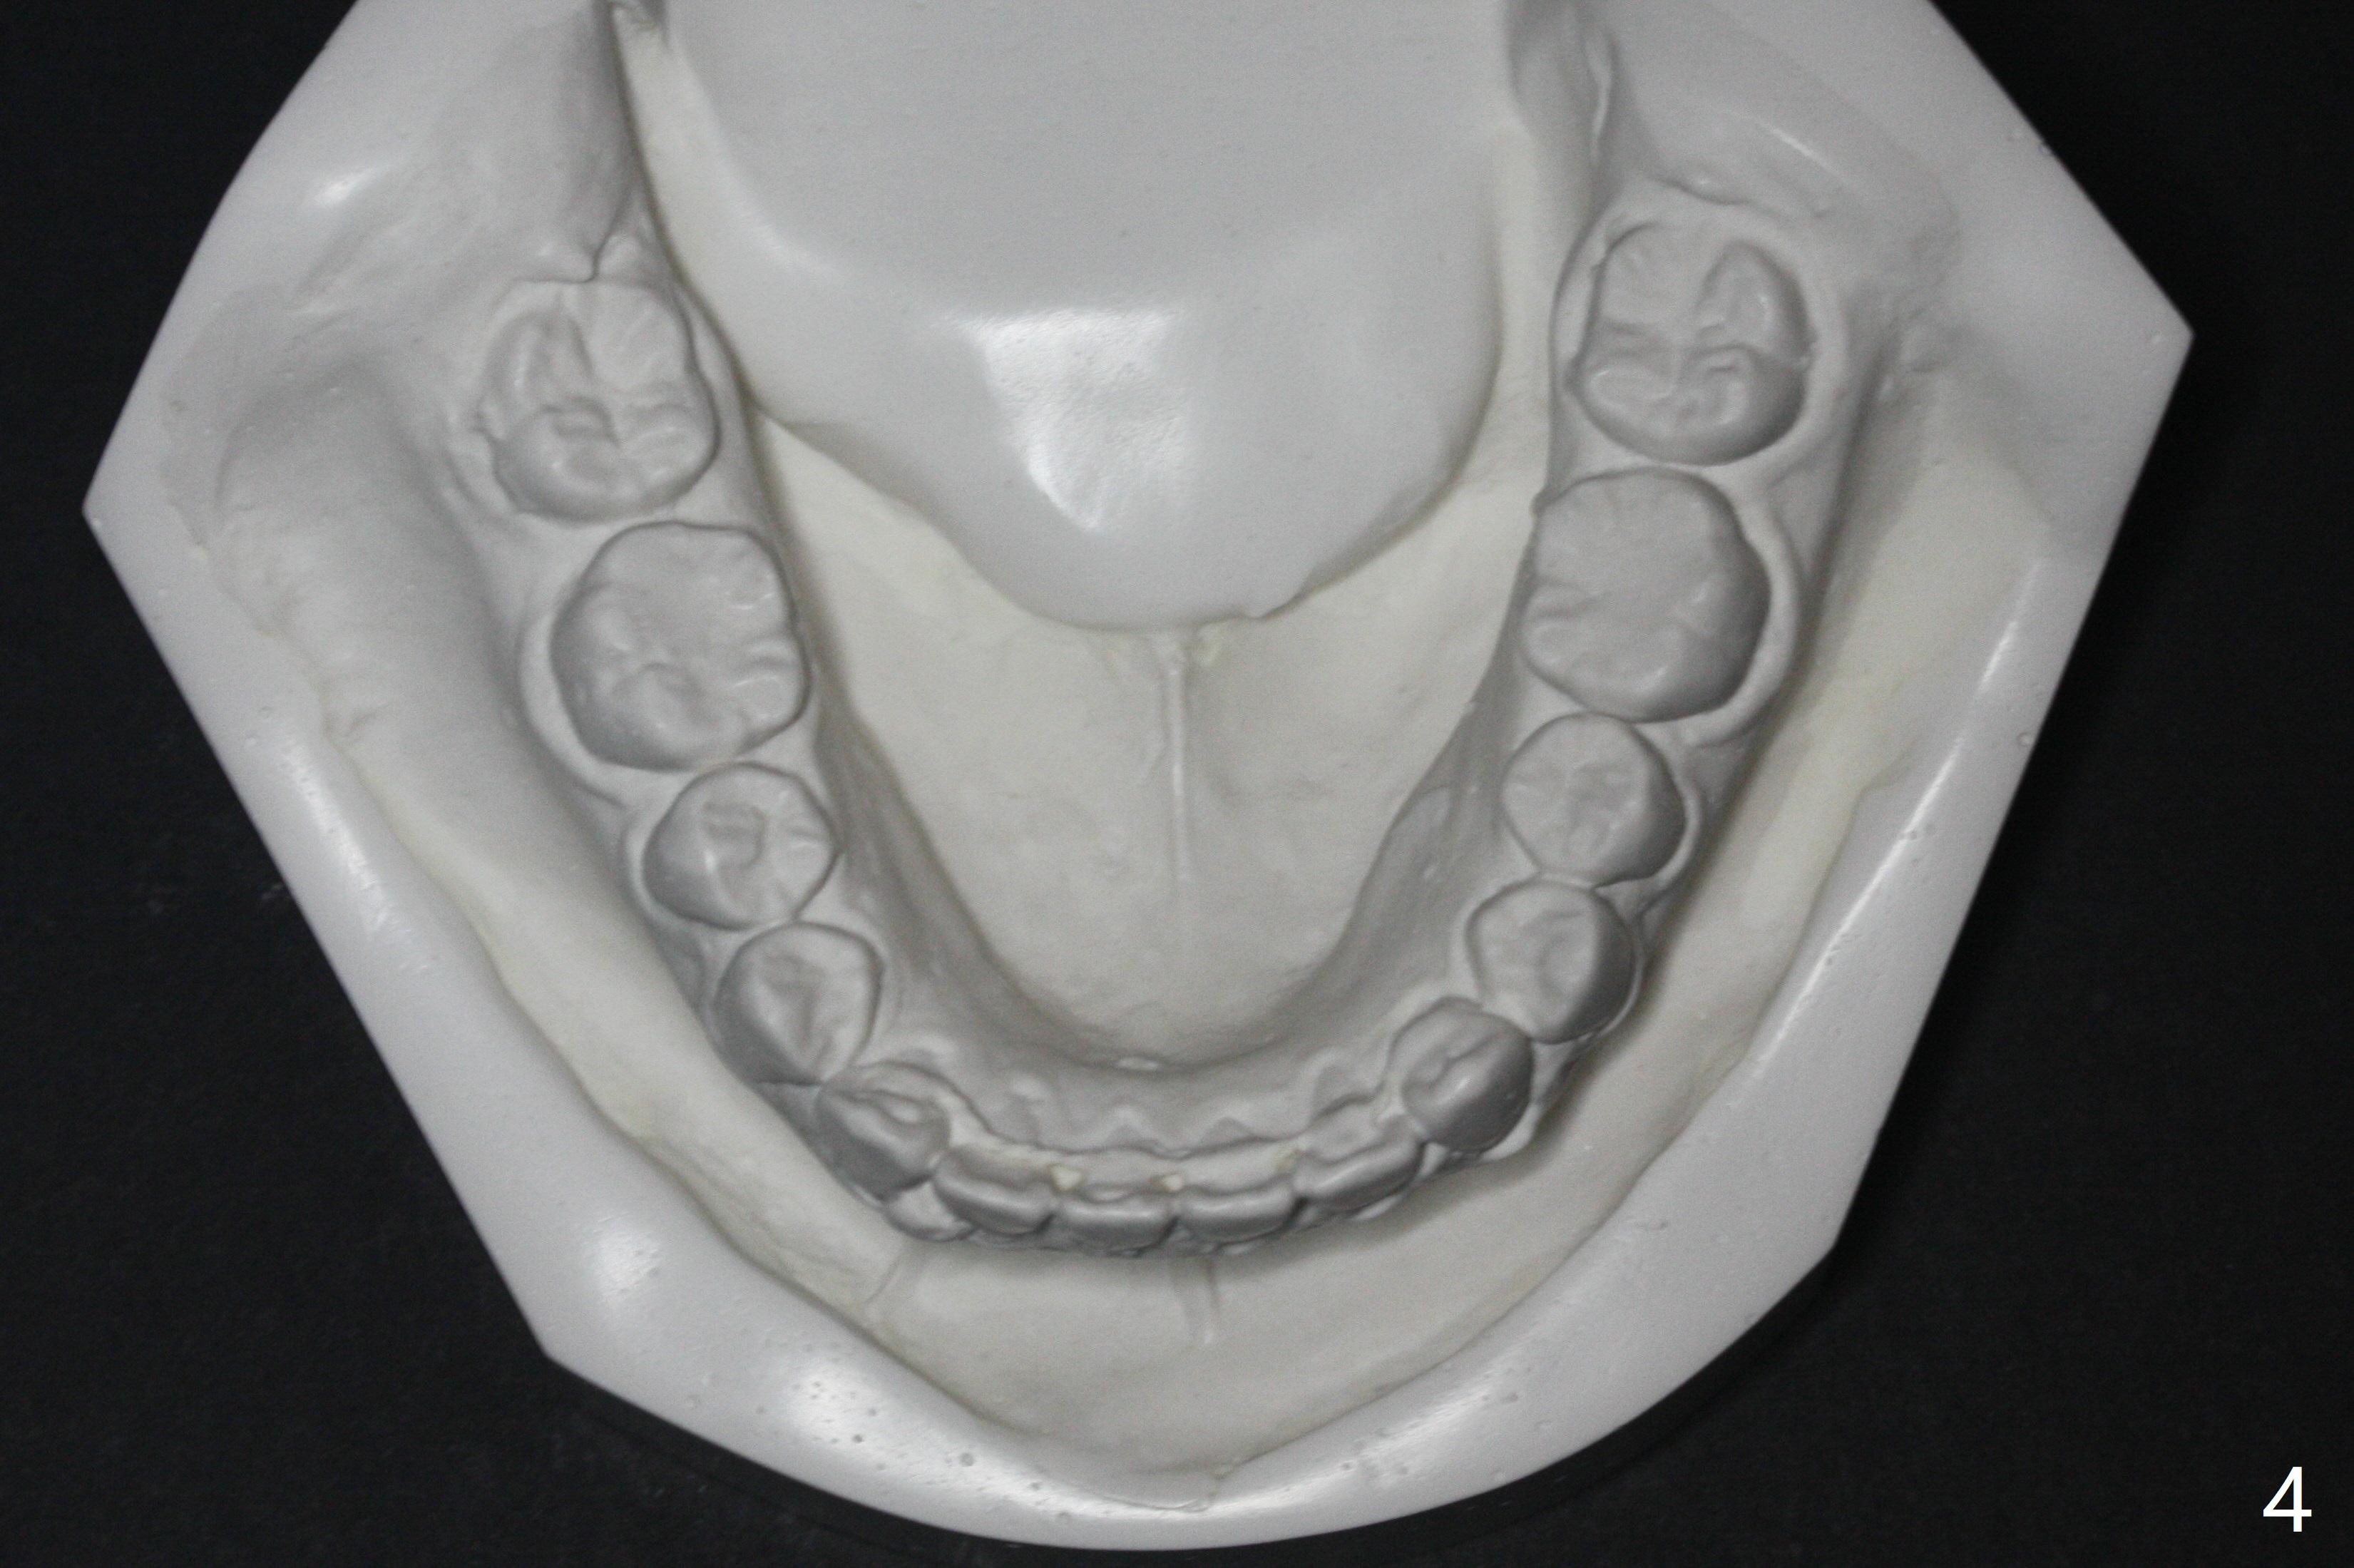

Since the lower anterior crowding is severe for a 15-year-old girl (Fig.2), lingual retainer is chosen for the lower arch (Fig.4), while a suck down one for the upper (Fig.1,3). No composite is applied to LR2 because the retainer wire adapts to the tooth nicely (Fig.4). In fact Dr. Shaughnessy does not apply composite to LL2 as well.